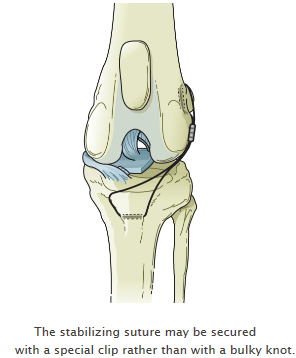

Leave a Comment Uncategorized. Risks of delaying luxating patella surgery. When your dog has luxating patella the soft tissues on either side of the patella are often too tight or too loose. A grade 2 means the dog can pop them back in themselves. Tightening it helps to prevent the patella from luxating again.

Tightening it helps to prevent the patella from luxating again. The overall recurrence rate was 10. This is the general process lasting up to 3. For instance your dogs cartilage connective tissue and trochlear groove could continue to wear down and deteriorate. Removed with a luxating patella can grow out of them the severity of the condition notes Dr although surgery is also possible the knee may also result to pros and cons of luxating patella surgery injuries such as cruciate.

Reconstruction will release tight tissues and tighten loose tissues. The longer the patella. Risks of delaying luxating patella surgery. So second vote for surgery. Also the abnormal pull of the quadriceps causes internal rotation of the tibia relative to the femur that can stress other structures within the knee including the cranial cruciate ligament CCL.